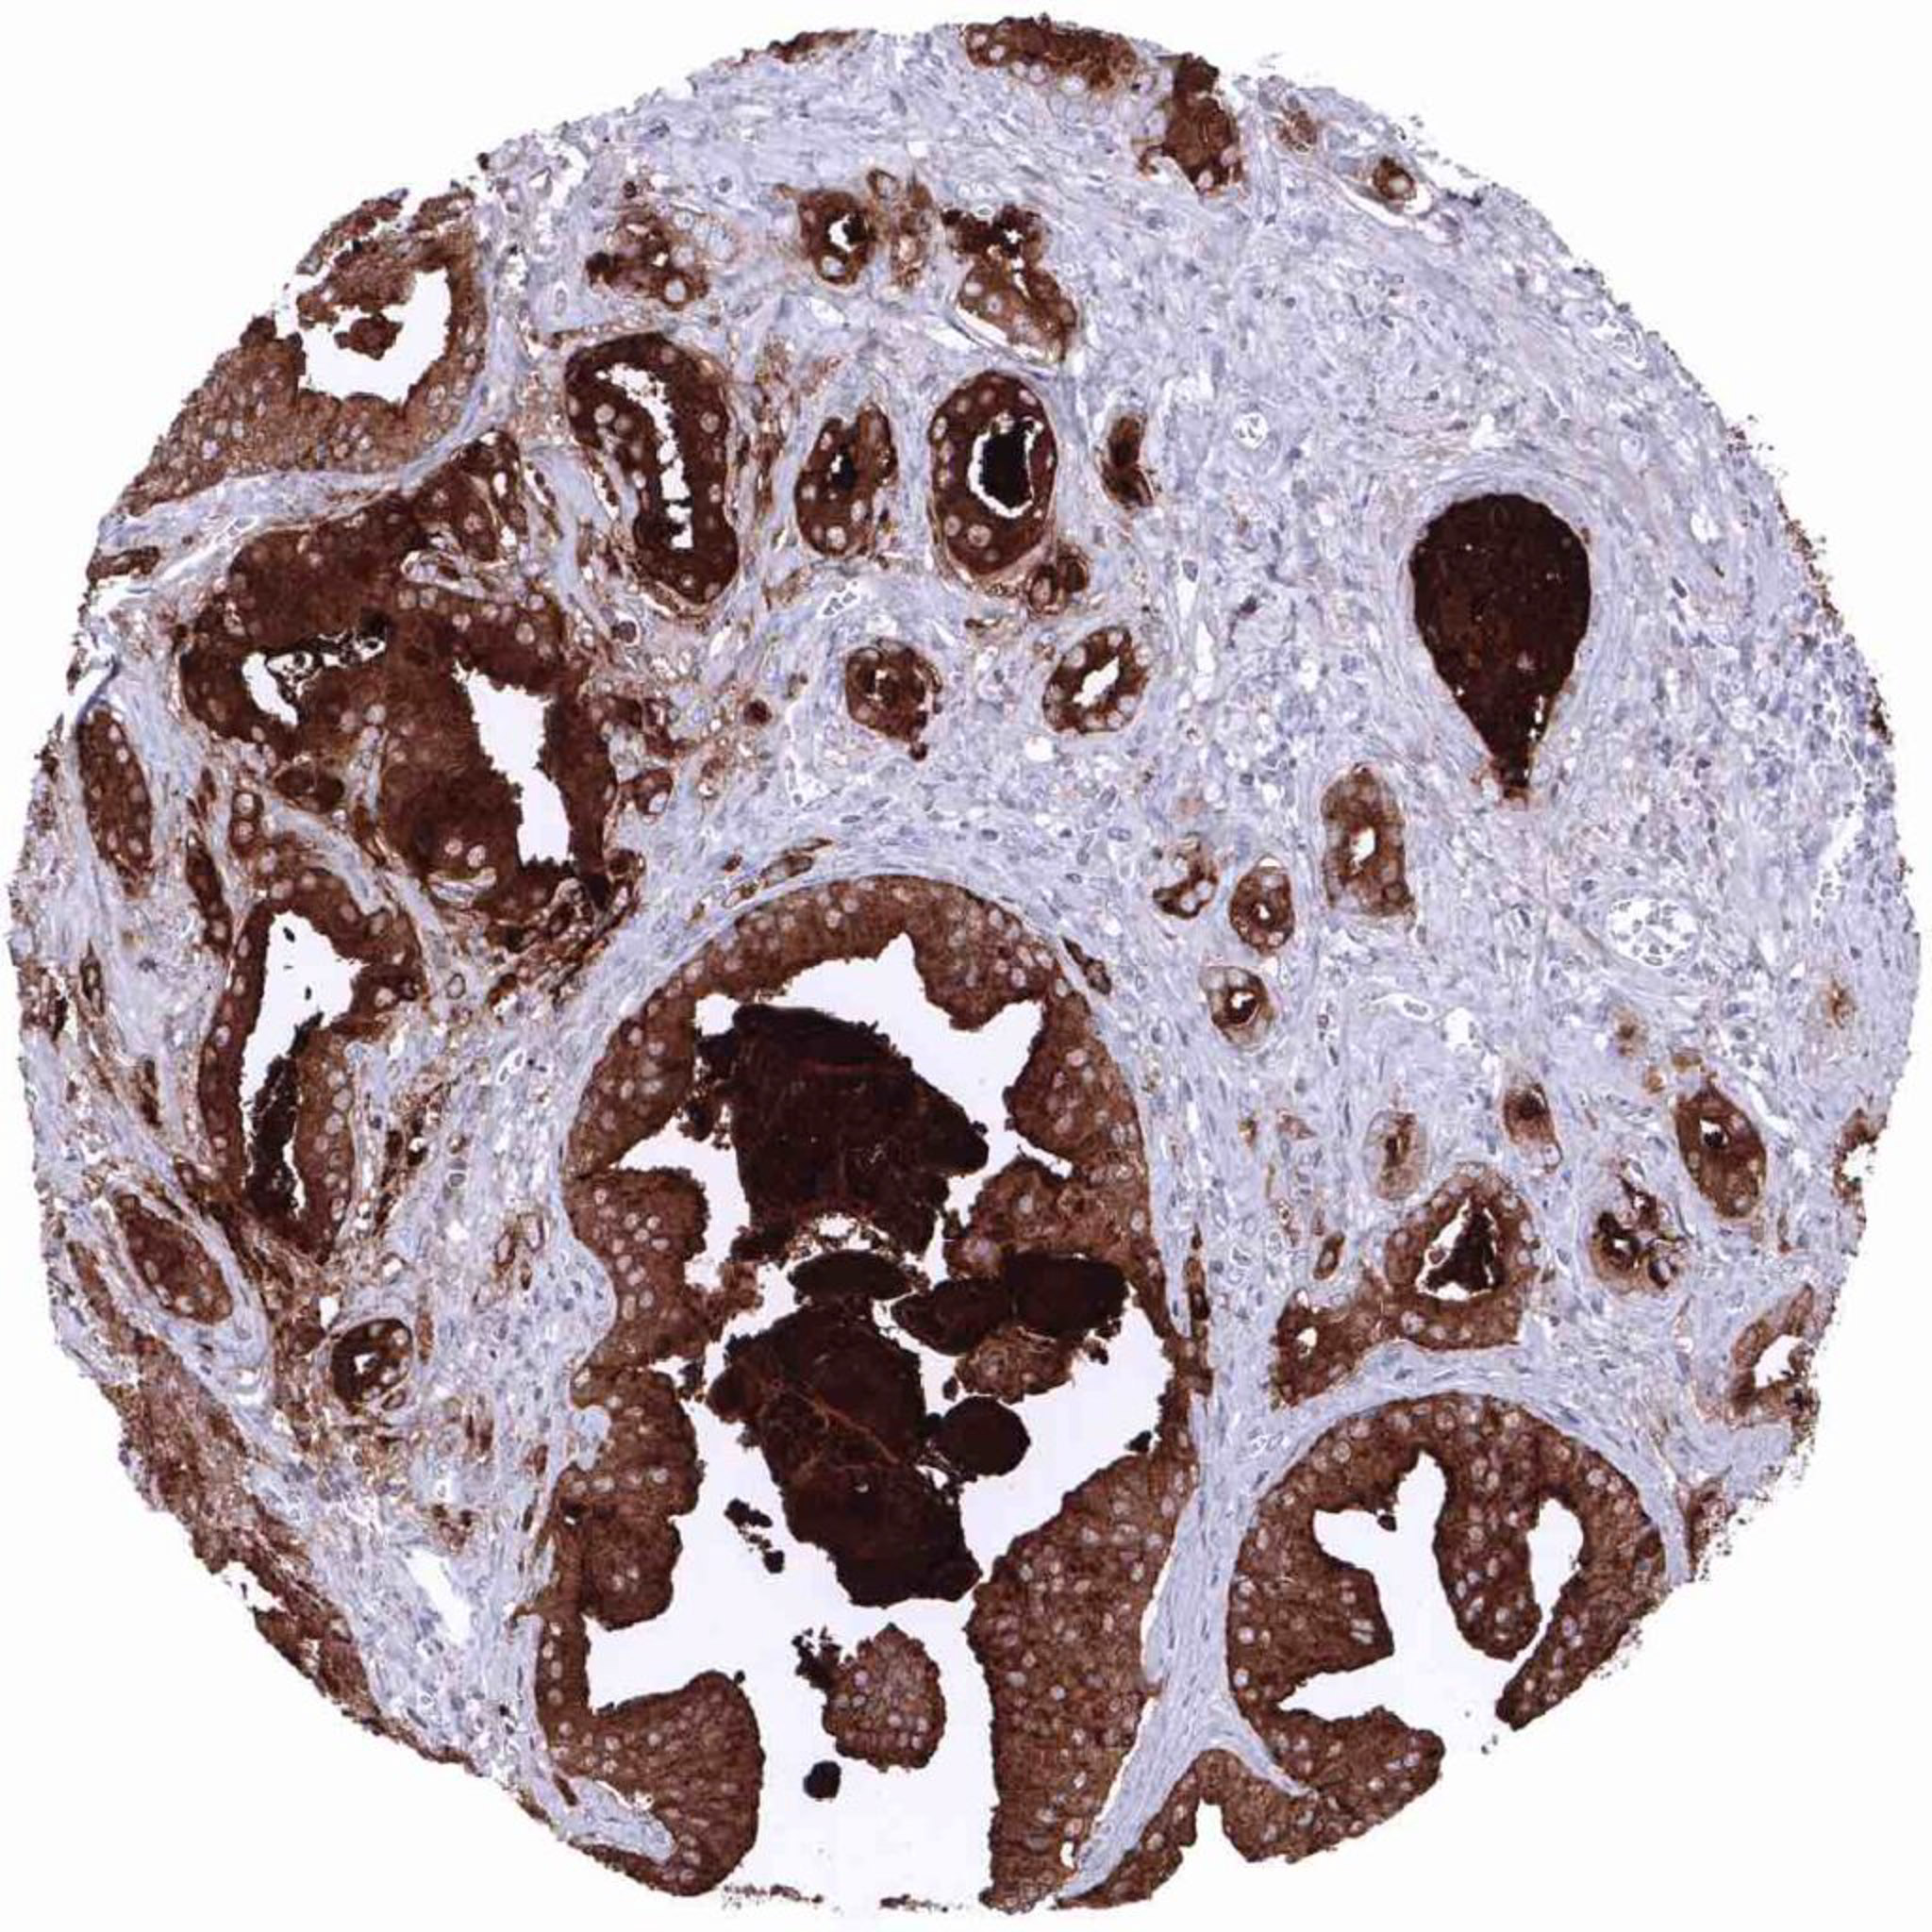

Prostate – Adenocarcinoma (Gleason 3+3=6) showing strong PSA positivity of tumor cells

Prostate – Adenocarcinoma (Gleason 3+3=6) with intense PSA immunostaining of tumor cells.

Prostate – Adenocarcinoma (Gleason 3+3=6) with strong PSA immunostaining of all tumor cells.

Prostate – Adenocarcinoma (Gleason 3+3=6) with strong PSA immunostaining of tumor cells